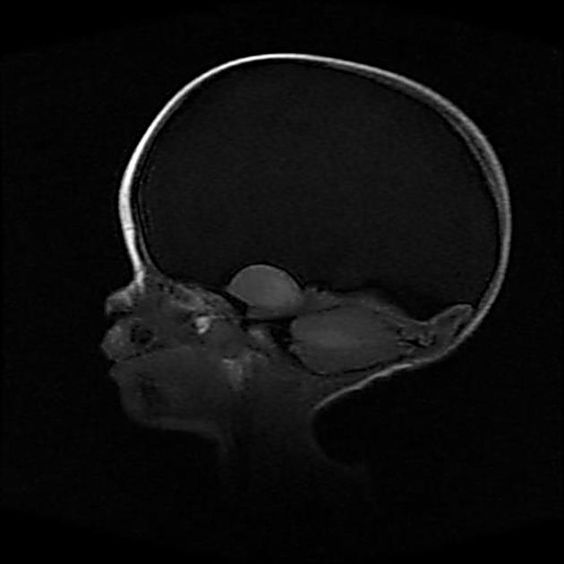

- КТ головного мозга – просматриваются структуры головного мозга, сосудистые сплетения, кости черепа и мозговые оболочки.

- Головы – черепа, придаточных пазух носа (ППН), орбит глаза, гипофиза, уха.

При подозрении на ишемический инсульт КТ является приоритетным методом диагностики. Внутривенное введение контраста позволяет не просто точно выявить очаг ишемии, с помощью него можно провести перфузионную КТ мозга, которая позволяет определить обратимость поражения ткани, установить давность инсульта, выявить коллатеральные пути кровоснабжения и определить поражение самых мелких церебральных сосудов.

КТ также легко выявляет гидроцефалию различного генеза. Признаками смешанной и наружной гидроцефалии является расширение субарахноидального пространства и желудочков (при смешанной), либо только субарахноидального пространства (при наружной).

Сотрясение головного мозга характеризуется кратковременным угнетением сознания- от нескольких секунд до нескольких минут, чаще в пределах оглушения. Применение КТ оправдано только при подозрении на ушиб мозга, так как у больных с сотрясением КТ не обнаруживает травматических отклонений в ликворосодержащих внутричерепных пространствах и состоянии вещества мозга (плотность серого и белого вещества остается в пределах нормы соответственно 33–45 и 29–36 единиц Хаунсфилда), то есть показывает норму на КТ.

Аппарат МСКТ из-за короткого времени сканирования позволяет избежать подобных артефактов, а легкие теперь обследуются всего за одну задержку дыхания. Внедрение ЭКГ-синхронизации, при которой срез делается только между сокращениями сердца, а также использование контрастного вещества позволило детально обследовать сердце, аорту и другие «пульсирующие» сосуды. Главное, достигнуто высокое пространственное разрешение с возможностью сканирования в любой плоскости с построением трехмерных изображений, что позволило аппарату МСКТ показывать онкологию с точностью до 0,5 мм, исследовать даже самые мелкие метастазы и выявлять распространенность процесса.